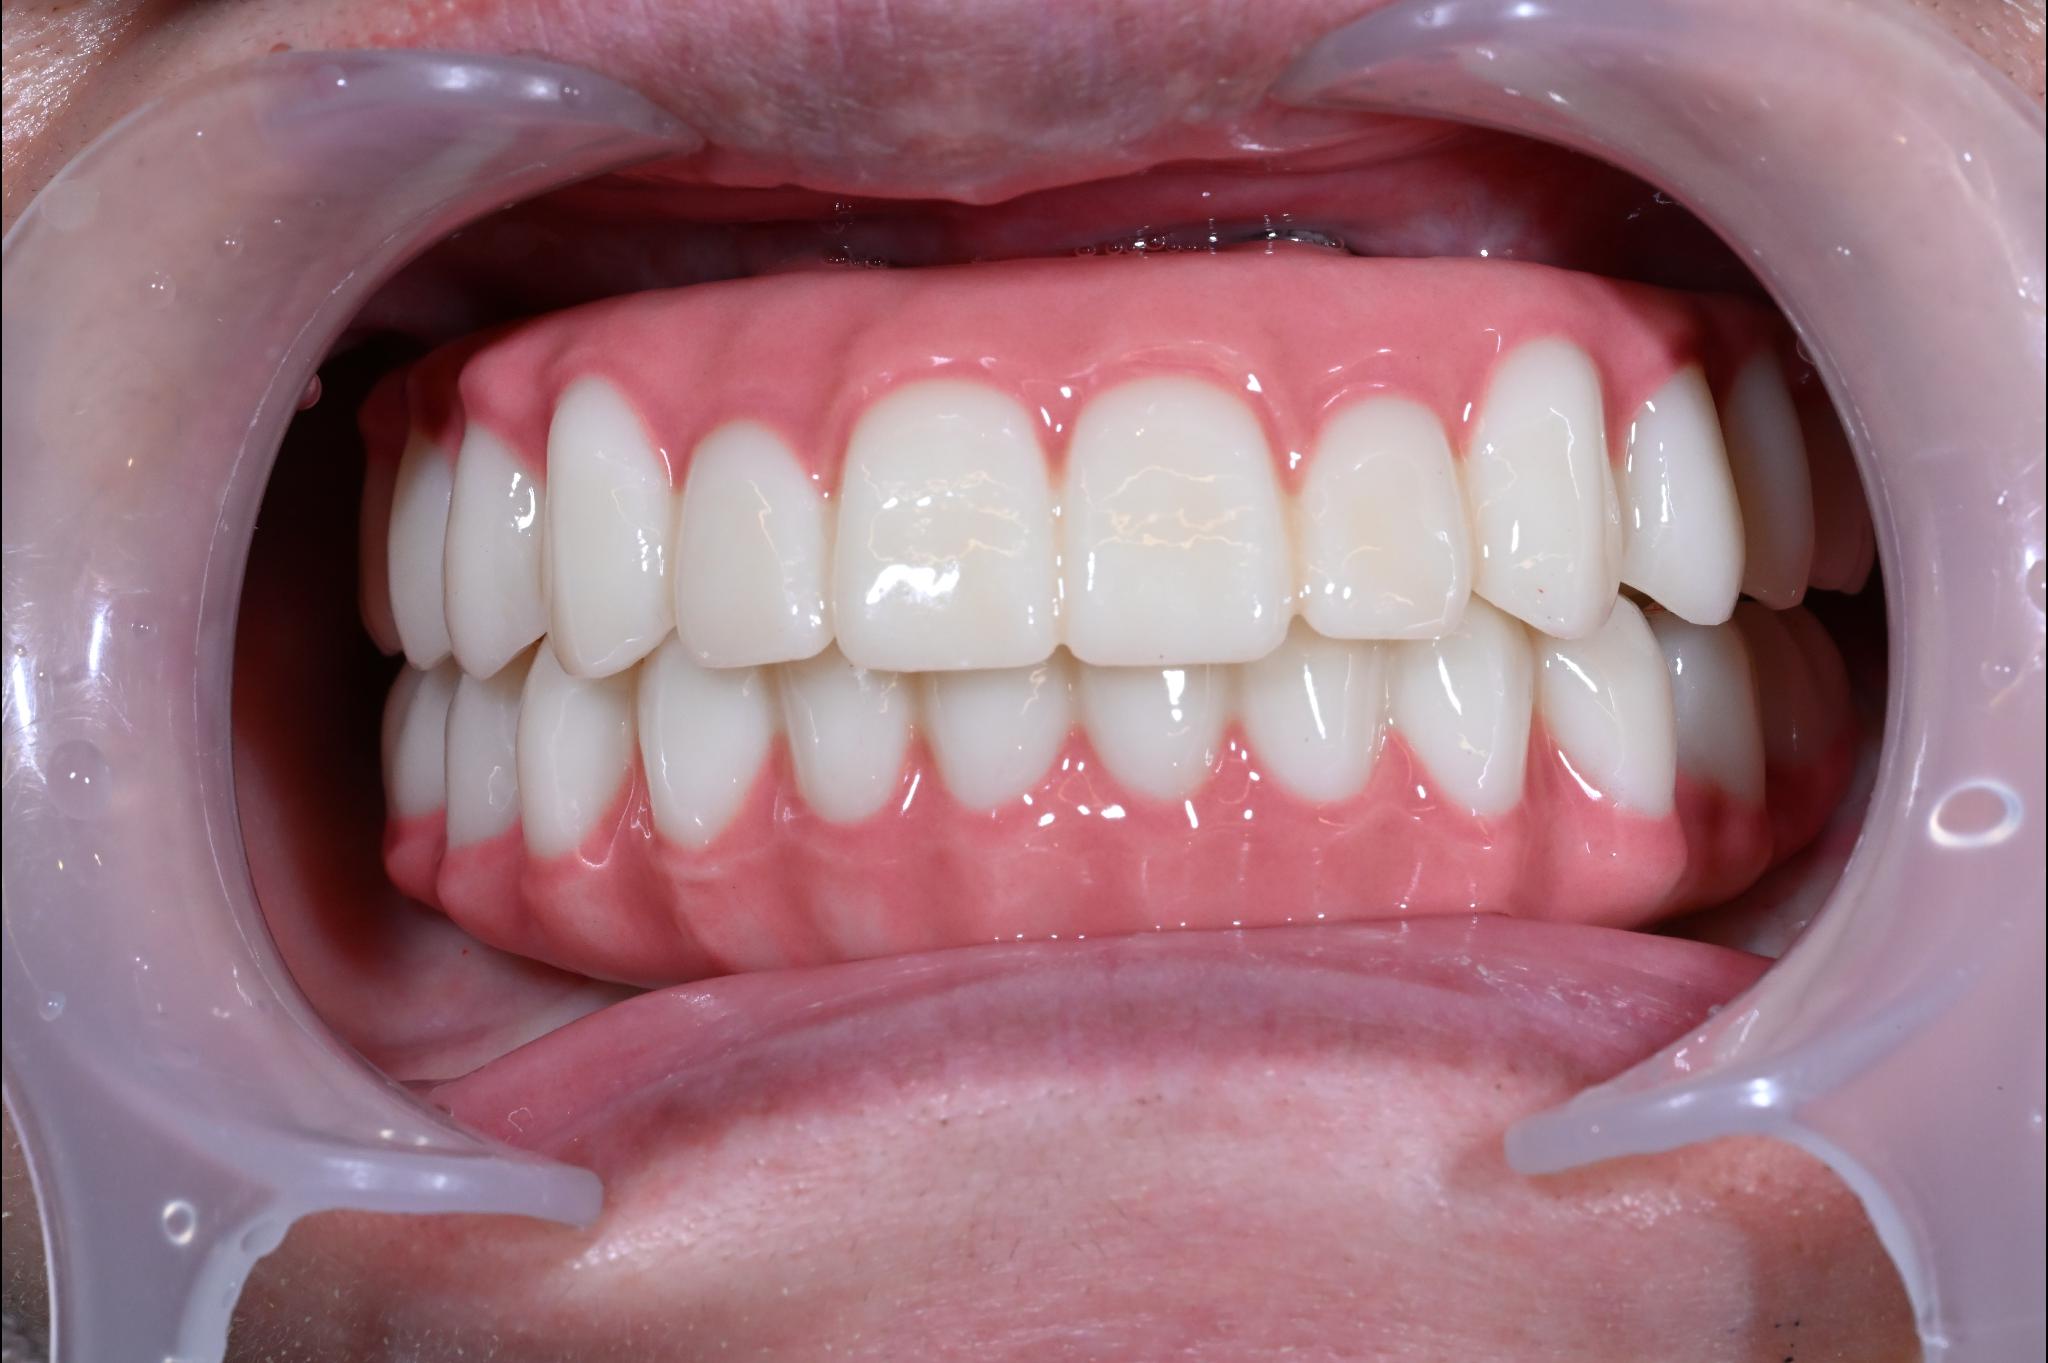

術後

内容 :上下顎オールオン4ザイゴマ0

費用 :4,365,900円

※モニター価格

期間 :半年

リスク:出血・腫れ・痺れ・痛み

「何度も通って恥ずかしい思いを長引かせたくない」という気持ちがありましたので、治療期間が短く、たった1日で固定式の歯が入ることがとても魅力的でした。

手術に対しては強い恐怖心を持っていましたが、実際には術中の記憶はほとんどなく、痛みを感じることもなく無事に終えることができました。

これまでは口元を気にして人との接触を避けていましたが、「笑顔で話したい」という明るい気持ちになれました。